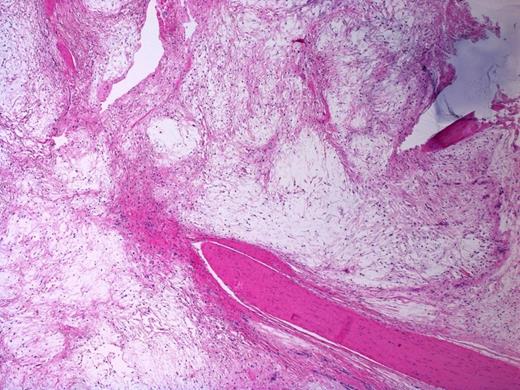

Multicystic appearance of the lesion with fibrous septa. H&E stain, 20X magnification

Sections of the lesion showed dense fibrous tissue with nodules of extracellular myxoid material containing scattered histiocytes and stellate to spindled fibroblastic cells. There was no evidence of necrosis, atypia or malignancy; this was consistent with Juxta-articular myxoma. (Figure 4 and 5). At one year follow-up there has been no sign of recurrence.